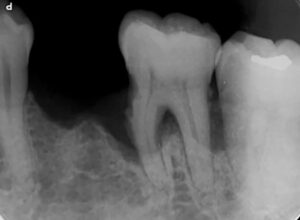

レントゲン写真を撮影すると、隣の第1大臼歯は重度の歯周病になっていたため、抜歯の後に2本のインプラントを検討すべき状況でした。

禁煙を承諾されない状況下では歯周病治療は難しく、重度歯周病の歯の隣にインプラントを埋入した場合、早期にインプラント周囲炎になる危険性を何度も説明しました。

患者様の選択は、「禁煙は出来ない。その代わりに歯磨きを徹底的に頑張るので、ダメ元で第1大臼歯の歯周病治療を行い、その結果を待ってから隣のインプラント治療をして欲しい」というものでした。

患者様の願いが天に通じたのか否かはわかりませんが、予想以上に歯周組織再生治療の効果が発現し、無事にインプラント治療を行うことができました。